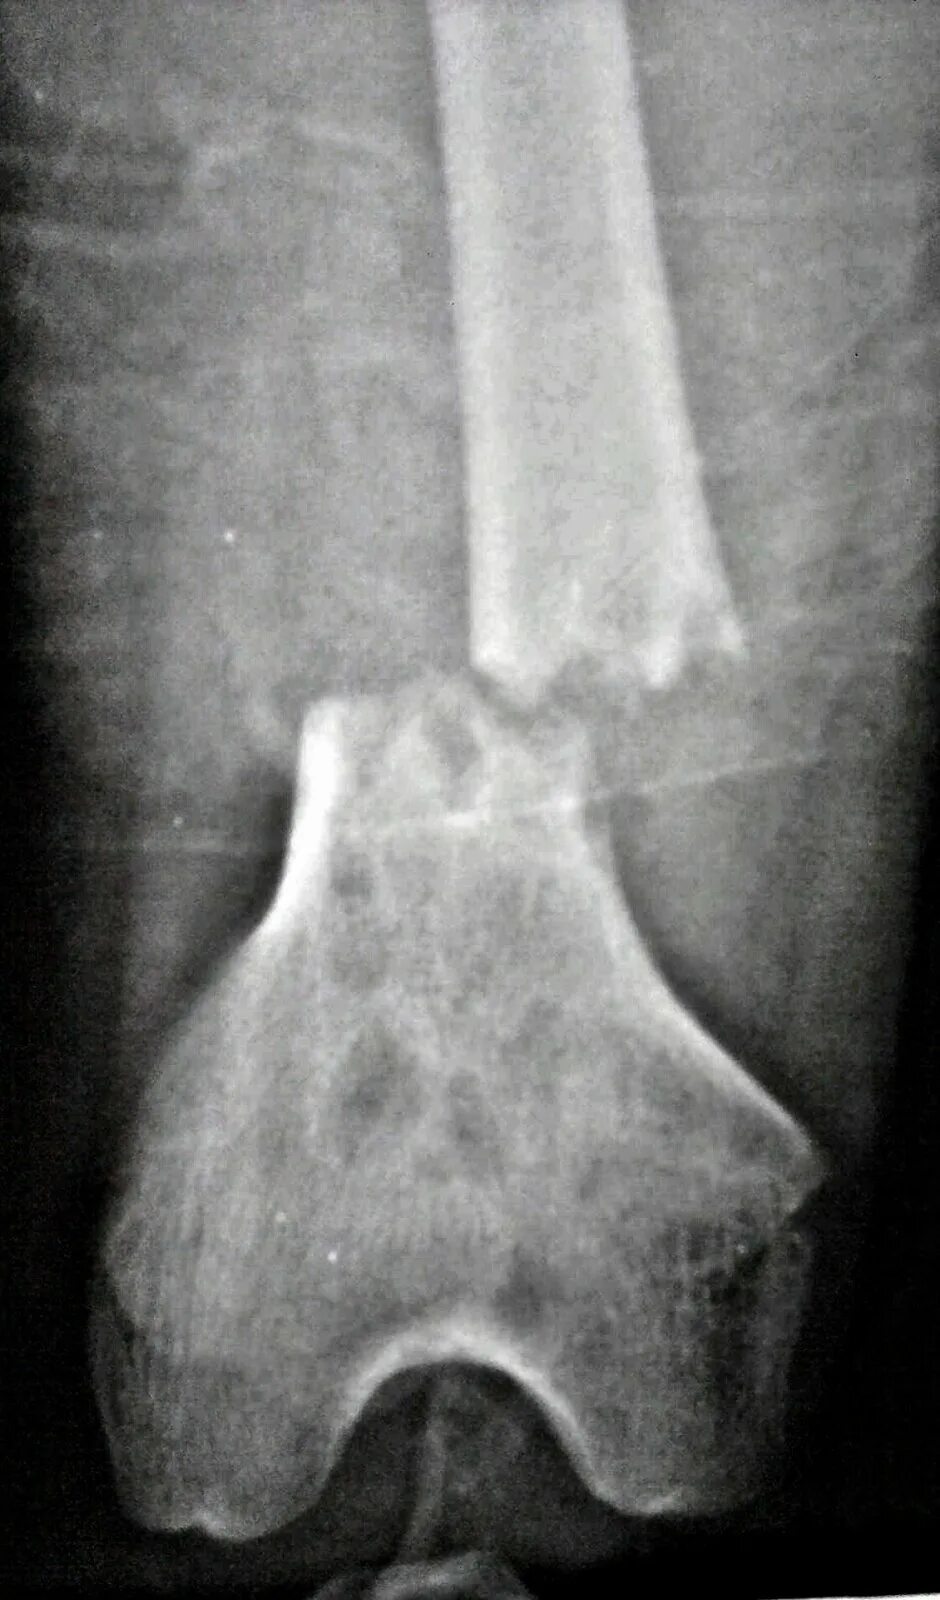

Патологический перелом бедра